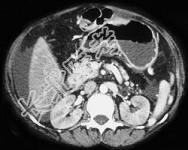

- 单项选择题如图,银染色可见系膜区及毛细血管袢有淀粉样物质沉积, 刚果红染色呈砖红色阳性,电镜以淀粉样纤维沉积为特点, 其病理诊断可考虑为 ( )